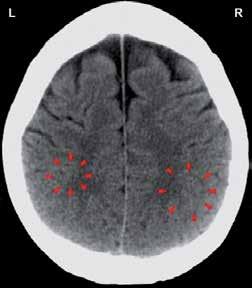

Zobje in telesni organi

Na sliki desno je shema povezav med zobmi in telesnimi organi, ki so jo naredili na Dr. Clark Research Slovenija (Drclark. si) po izsledkih več tisočletij starih spoznanj tradicionalne kitajske medicine. Denimo, levi zgornji modrostni zob (št. 28) je povezan z meridianom tankega črevesa in srca. Zaradi bolnega zoba in zatorej motenega pretoka čija čez ta meridian imamo lahko migrene, epilepsijo, težave s srednjim ušesom, rameni, komolcem, možgani, hrbtenjačo, krvjo, venami in arterijami. Njihova še podrobnejša shema, ki je dostopna na misteriji.si/blog/cat/pomoc_ pri_zdravju/, pa razkriva, da lahko to izzove tudi vremensko občutljivost, vremenski glavobol, mišično distonijo (krčenje mišic), multiplo sklerozo, možganski tumor, motnje vitalnosti, izostanek glasu po daljšem govoru, išias, glavobole, zvonjenje v ušesih, zamrznjeno ramo, vnetje obraznega živca, vnetje vidnega živca. Če je ta zob mrtev, pa so težave še toliko hujše.